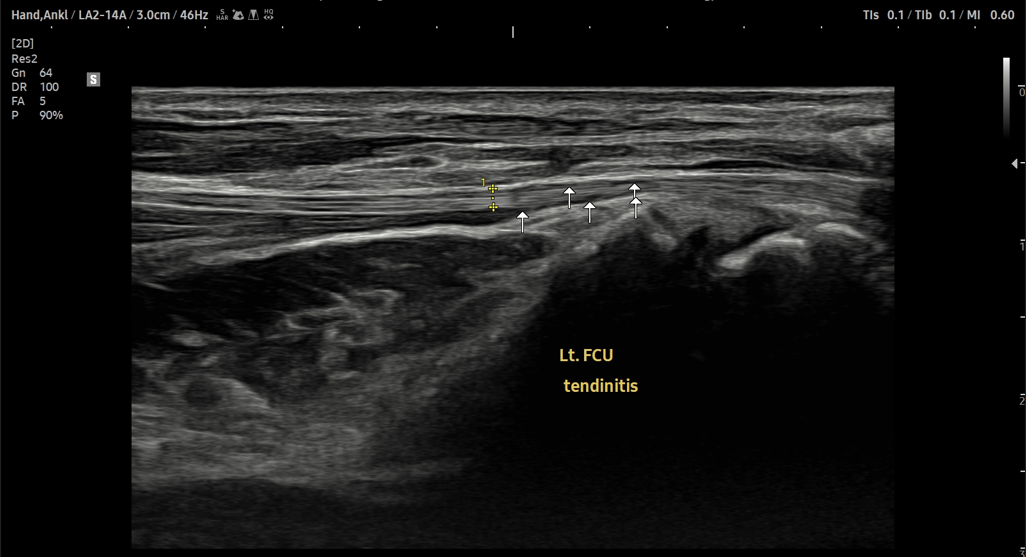

- 치료기간 : 25 . 8 . 19 ~ 25 . 10 .24

- 치료횟수 : 11 회(아피톡신+극초단파)

마지막 치료 이후 내원이 어려우셔서 유선상 확인